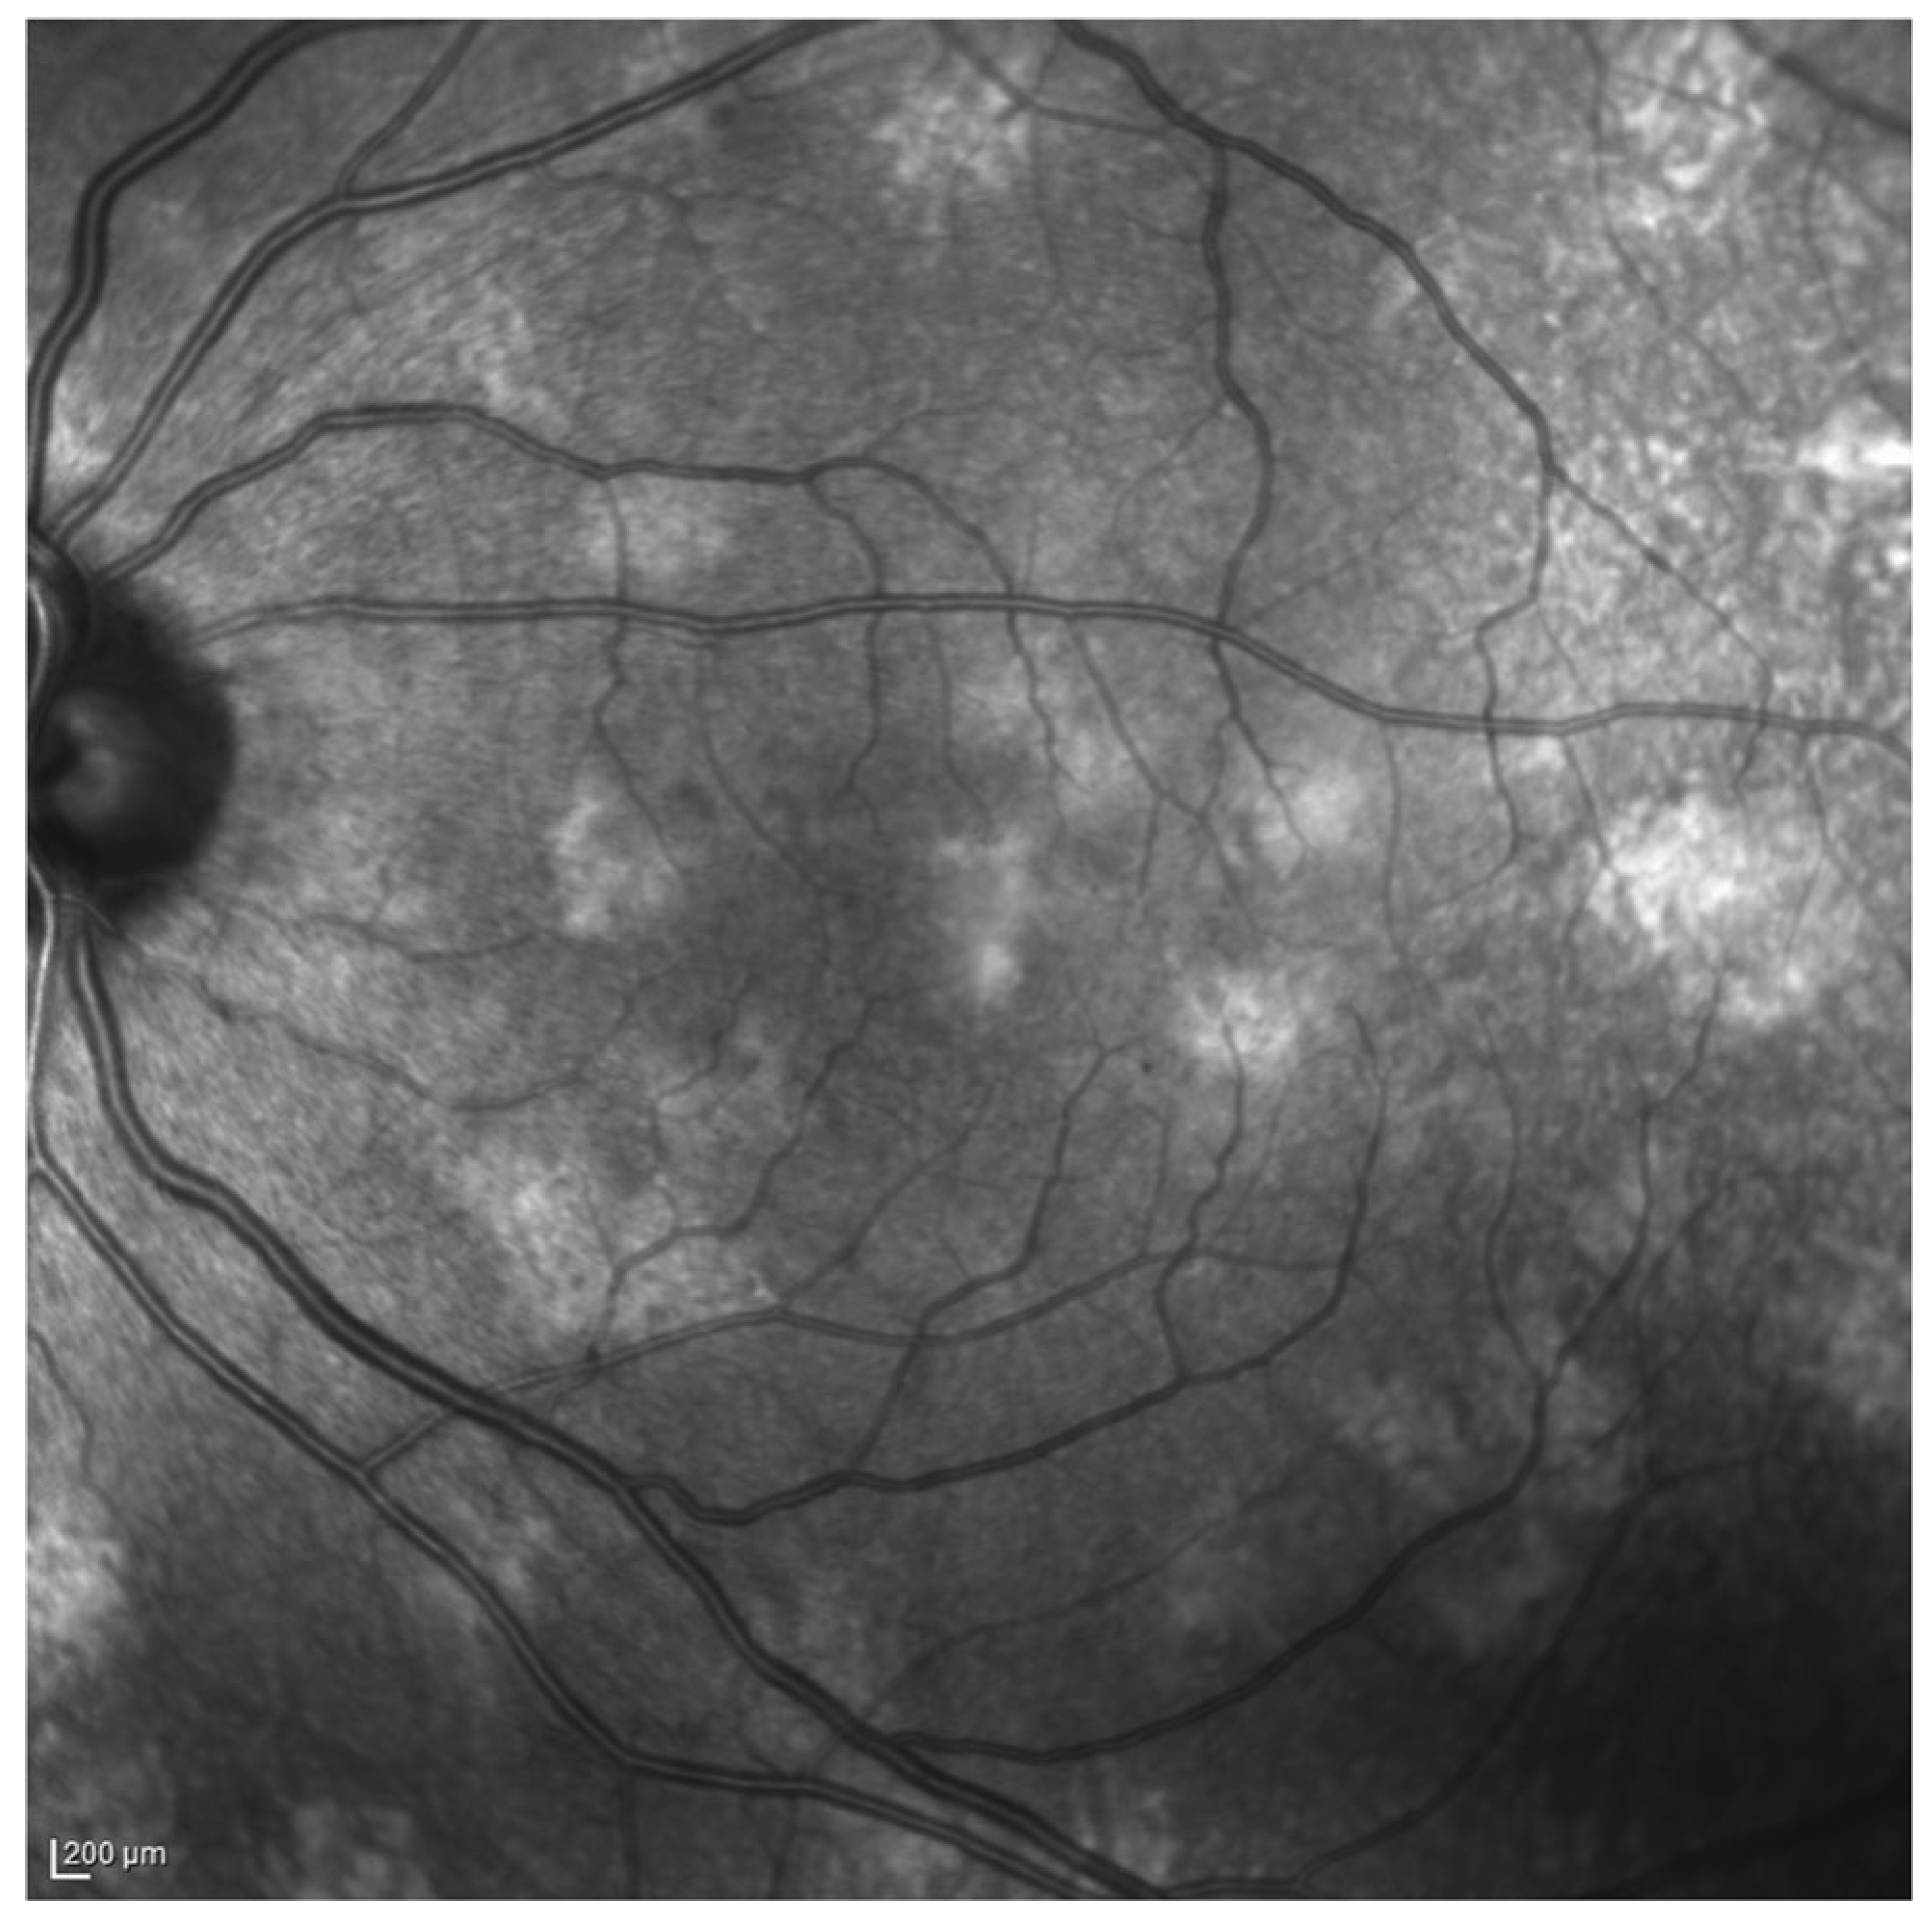

- Moramarco, A.; Giustini, S.; Nofroni, I.; Mallone, F.; Miraglia, E.; Iacovino, C.; Calvieri, S.; Lambiase, A. Near-infrared imaging: An in vivo, non-invasive diagnostic tool in neurofibromatosis type 1. Graefe’s Arch. Clin. Exp. Ophthalmol. 2018, 256, 307–311. [Google Scholar] [CrossRef]

- Moramarco, A.; Giustini, S.; Miraglia, E.; Sacchetti, M. SD-OCT in NIR modality to diagnose retinal microvascular abnormalities in neurofibromatosis type 1. Graefe’s Arch. Clin. Exp. Ophthalmol. 2018, 256, 1789–1790. [Google Scholar] [CrossRef]

- Mallone, F.; Lucchino, L.; Giustini, S.; Lambiase, A.; Moramarco, A. An update on choroidal abnormalities and retinal microvascular changes in neurofibromatosis type 1. Orphanet J. Rare Dis. 2022, 17, 223. [Google Scholar] [CrossRef]